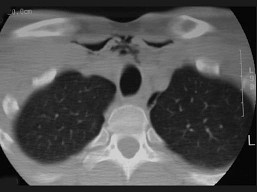

11.27岁男性,开车外出在高速行驶时翻车,呼吸困难,喉部肿胀,CT检查如图所示,请选择正确的描述或诊断 ( )![]() ![]() ![]() ![]() |

| 正确答案:ABCE |